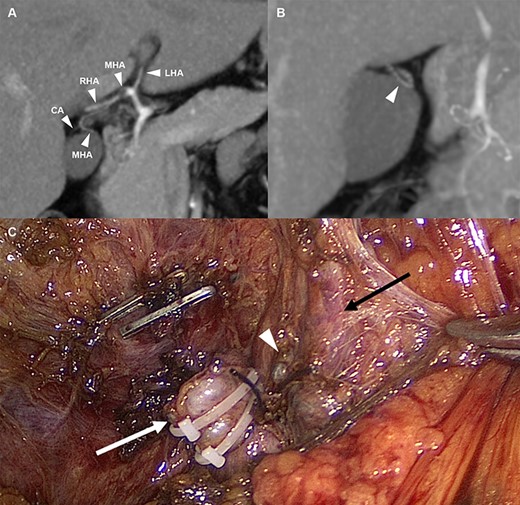

(A) Arterial anatomy; the MHA derived from the hilum of the hepatic artery and the CA arising from the MHA (B) The MHA that runs into segment IV (C) Anatomical structures after cholecystectomy; white arrow: cystic duct stump, white wedge: CA stump, and black arrow: MHA. LHA, left hepatic artery; MHA, middle hepatic artery; RHA, right hepatic artery; CA, cystic artery.

Keeping in mind this anatomical variation, laparoscopic cholecystectomy was performed. Moderate adhesion around Calot’s triangle was observed due to previous colic attacks. The omentum, round ligament and gallbladder were adhered to each other, and it was difficult to separate each of them. After careful dissection of the medial border of the gallbladder, the MHA that ran to segment IV was observed. Dissecting downward along the MHA, a cystic artery was observed around the cystic duct. The cystic artery and duct were isolated and each was separately ligated and cut. The gallbladder was detached from the liver and hemostasis was achieved. After insertion of a drainage catheter into the subhepatic space, abdominal closure was performed. The patient was discharged on postoperative Day 5 without any adverse events.